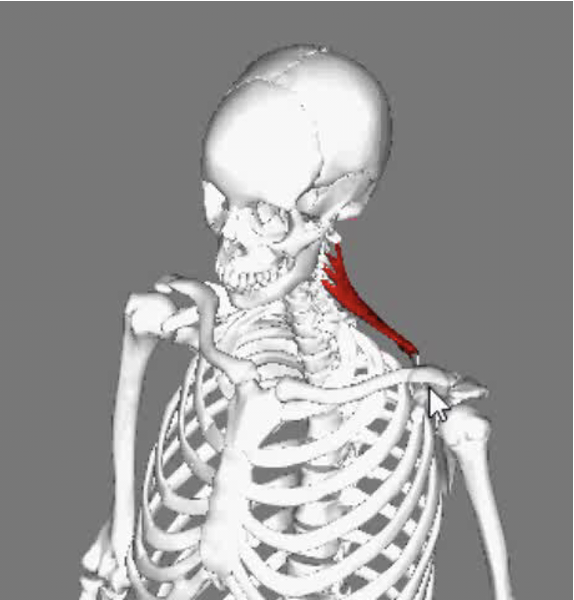

Splenius Capitis

Splenius capitis forms part of the floor of the posterior triangle of the neck, above and behind levator scapulae; it is deep to the rhomboideus and trapezius.

- Origin

- It is attached proximally to the lower half of the ligamentum nuchae, spinous processes of C7 to T4 and intervening supraspinous ligaments.

- Insertion

Action

- Individually

- Extends the head and neck, accompanied by lateral flexion of the neck and rotation of the face to the same side.

- Together

- Pure extension

Splenius Capitis/Cervicis

- Midway between the inion and mastoid process

- From the same attachment forward is SCM

- Runs obliquely to spinal processes of C7 to T3

- Cervicis runs lateral border and underneath capitus anterior to levator scapulae.